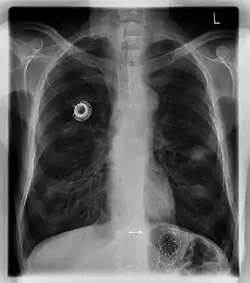

Portkatheter

Ein Portkatheter bzw. ein Portsystem (von lateinisch porta, „Pforte“) ist ein unter der Hautoberfläche liegender (subkutaner), längere Zeit verwendbarer Zugang für Infusionen.

Ein Portkatheter besteht aus einer unter der Haut liegenden Kammer, die Port genannt wird und die mit einer dicken Silikon-Membran (Septum) versehen ist, sowie einem daran bei der Implantation anzuschließenden Schlauch (Katheter). Die Portkammer kann entweder aus Titan, Edelstahl, Keramik, Kunststoff oder aus einem Verbundwerkstoff der vorgenannten Materialien bestehen. Der Katheter besteht beispielsweise aus Silikon oder Polyurethan.[1]

Die häufigste Variante ist der venöse Portkatheter (Venenport), bei dem wie bei zentralvenösen Kathetern bei der Implantation der Katheterschlauch in eine der großen Venen im Brustraum im Zustrombereich des Herzens eingeführt wird, sodass sein offenes (distales) Ende kurz vor dem rechten Vorhof des Herzens zu liegen kommt.

Bei allen Verfahren erfolgt eine Röntgen-Angiografie zur Lagekontrolle des Katheters, auch zur Dokumentation des Eingriffes. Dann wird der Katheter auf die außerhalb der Vene bis zur finalen Position der Portkammer in der Hauttasche erforderliche Länge gekürzt und mit der Portkammer verbunden. Im nächsten Schritt wird die Portkammer in der Hauttasche an der darunter liegenden Faszie angenäht. Danach wird der Hautschnitt chirurgisch geschlossen (vernäht). Mit der Rippe als „Widerlager“ kann der Port von nun an punktiert („angestochen“) werden.